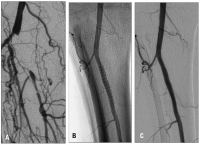

Ischämie

Abbildung 3a-b: A. Kritische Ischämie bei Verschluß des Truncus tibiofibularis. B. Nach Implantation eines Cypher 3,5/33 mm-Stents. C. 6-Monats-Follow-up.